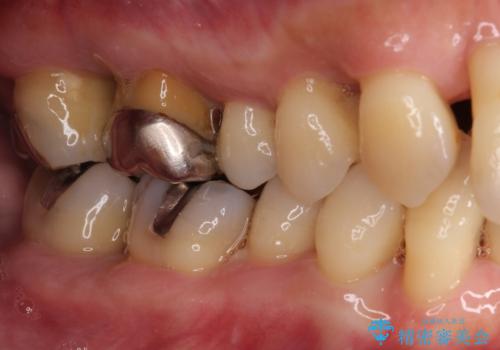

歯周初期治療として抜歯や歯槽骨再生治療を行い、さらに歯周ポケット除去を行った後に矯正治療で歯列を整えて行くこととしました。

2~3年は早く終了する予定でしたが、途中で体調を崩されて来院されない時期が続いたため、非常に長期間の治療となりました。

上顎口蓋からの堅い歯肉を移植する角化歯肉移植術を行いたかったのですが、体調不良から実施しなかったため、最終補綴物であるオールセラミッククラウンを装着した後に、知覚過敏や境目が見てしまうといった問題が一部で発生いたしました。